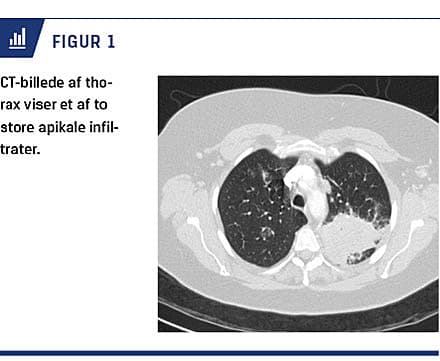

En 54-årig kvinde blev henvist til cancerudredning pga. tre måneder varende influenzalignende symptomer, træthed, hoste, hæmoptyse, ledsmerter og et vægttab på 3 kg. Der viste sig også at være recidiverende otitis media, hyppige forkølelser med blodigt sekret fra næsen og hævede ben. Biokemiske undersøgelser viste en sænkningsreaktion på 100 mm/t, leukocytniveau på 18 × 109/l og hæmoglobinniveau på 7 mmol/l. En ekkokardiografi udført på mistanke om hjerteinsufficiens viste normale forhold. CT af thorax, abdomen og bækken viste på henholdsvis højre og venstre side to store apikale infiltrater (Figur 1), som siden også viste sig at være fluordeoxyglukose-PET/CT-positive. Man planlagde videre udredning med biopsi på en lungemedicinsk afdeling. Inden patienten blev indkaldt til dette, blev hun indlagt på en internmedicinsk afdeling seks dage efter den primære kontakt pga. tiltagende ledsmerter, hævelse af hænderne samt nedsat følesans og kraft i underekstremiteterne. Objektivt fandt man splinters og hudblødninger i fingerpulpae, og de neurologiske gener blev bekræftet. Der var svært forhøjet C-reaktivt protein-niveau på 263 mg/l, og man indledte bred-